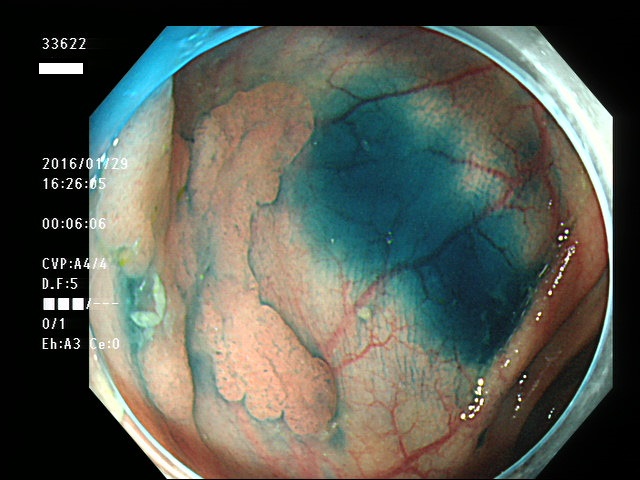

上記100名より抽出した平坦・陥凹型腺腫(=癌化の危険が高いが見落としやすい病変)の内視鏡写真